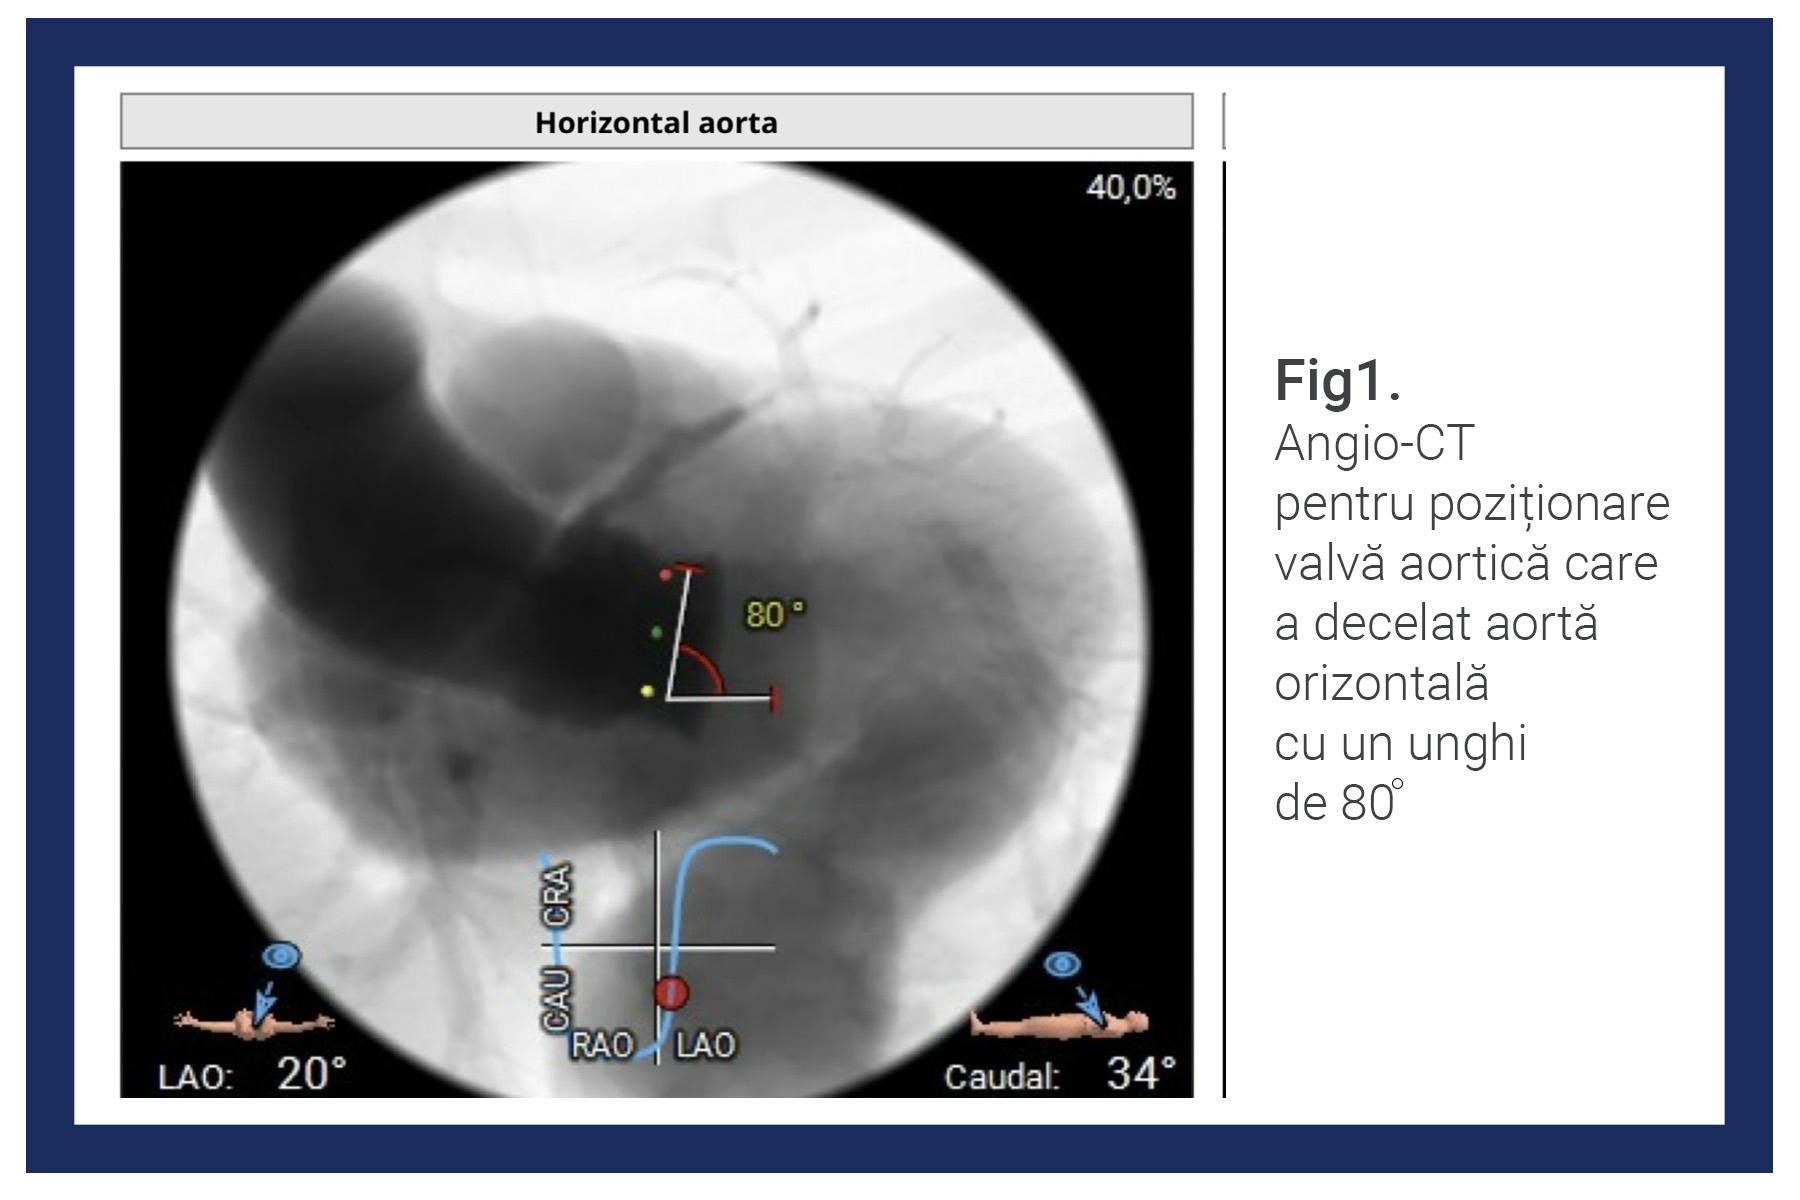

În timpul investigațiilor suplimentare premergătoare intervenției de implantare de valvă aortică, medicii au descoperit că anatomia aortei este diferită decât în mod obișnuit și are un unghi mai mare (80 de grade), situație care face ca procedura să fie mai complicată.

Imaginile CT au arătat, de asemenea, că există și un anevrism de aortă toraco-abdominal, adică o umflătură la nivelul aortei din zona toracelui și abdomenului, ceea ce a adăugat și mai multă complexitate.